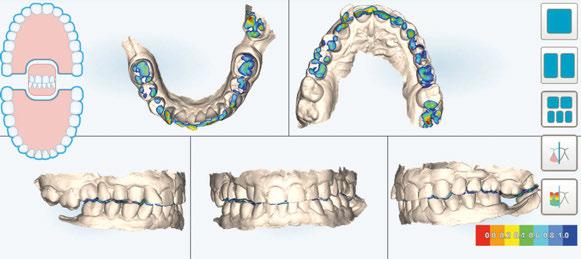

A los 4 meses, se retiró la prótesis provisional, verificando la

estabilidad de todos los implantes y procediendo a la toma de impresión definitiva, enviando toda la información necesaria, tanto de la posición de los implantes, de los perfiles de emergencia y pónticos y de la forma del provisional (Figuras 28 y 29).

Para ello, se procedió al escaneado mediante el escáner intraoral iTero Element™2 de los siguientes elementos:

Figura 28. Provisional en boca a los 4 meses.

Figura 29 (a, b, c). Perfiles de emergencia tras la retirada del provisional.

-Escaneado 1 superior (preescaneado): provisional atornillado en boca.